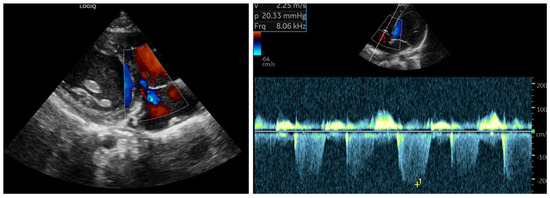

Background and Clinical Significance: Scurvy, caused by chronic vitamin C deficiency, is re-emerging in Western countries, particularly among pediatric patients with highly selective diets. While its musculoskeletal and mucocutaneous manifestations are well-known, its association with pulmonary arterial hypertension (PAH) is rare and poorly understood. Ascorbic acid and iron are essential cofactors for prolyl hydroxylases (PHD), which regulate Hypoxia-Inducible Factors. Their combined deficiency may trigger a “pseudohypoxic” state, leading to pulmonary vascular remodeling and vasoconstriction. Case Presentation: A 30-month-old female presented with a one-month history of limping, lower limb pain, and gingival hypertrophy. Dietary history revealed an almost exclusive cow’s milk-based intake. Physical examination showed diffuse petechiae, pallor, and right knee edema. Laboratory findings confirmed scurvy (undetectable vitamin C), severe iron-deficiency anemia (Hb: 72 g/L; ferritin: 22 mcg/L; RDW: 30%), folate deficiency, and hyperhomocysteinemia. Notably, elevated copper and vitamin B12 levels suggested a state of metabolic dysregulation. Echocardiography revealed moderate PAH phenotype (estimated sPAP: 47–50 mmHg) and a hyperdynamic contractility. A “perfect storm” mechanism was hypothesized, involving iron–ascorbate-dependent PHD impairment, high-output state, and oxidative-stress-induced hepcidin dysregulation (suggested by elevated copper). Following intravenous vitamin C and multivitamin supplementation, pulmonary pressures normalized within one week. Conclusions: PAH phenotype in scurvy represents a reversible metabolic disruption of pulmonary vascular tone rather than a structural disease. This case underscores the synergistic role of vitamin C, iron, and folate in vascular homeostasis. Clinicians should maintain high suspicion for scurvy in children with selective diets and unexplained PAH, as nutritional restoration is curative. Full article